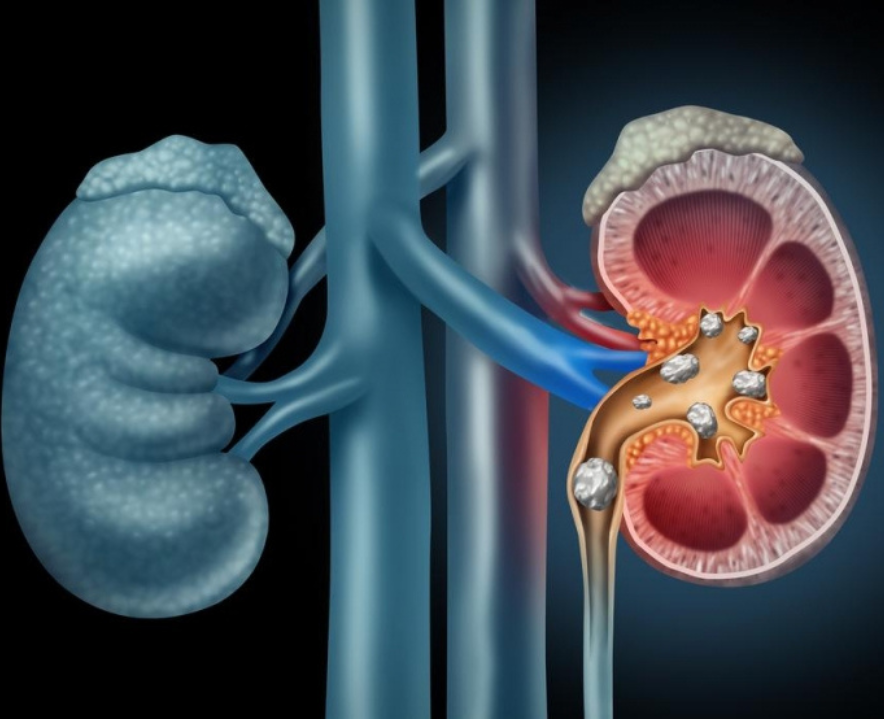

Kidney stones are hard deposits of minerals and acid salts that form in your kidneys. It is formed due to various reasons. They can affect the kidney, the urethra, bladder

Read More